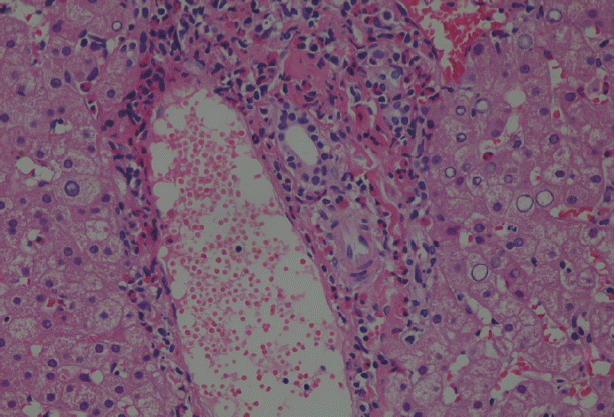

Because malignancy was initially considered, laparoscopic liver biopsy under visual control was performed at the Department of surgery on 23 June 2016. The liver biopsy was then obtained which showed liver tissue with eosinophil accumulation around the hepatobiliary system. Moreover, a detailed re-evaluation of liver biopsy in National Institute of Parasitic Diseases, Chinese Center for Disease Control and Prevention (NIPD) (15 August 2016) revealed histopathological features suggesting a parasitic infection (Fig. 2).